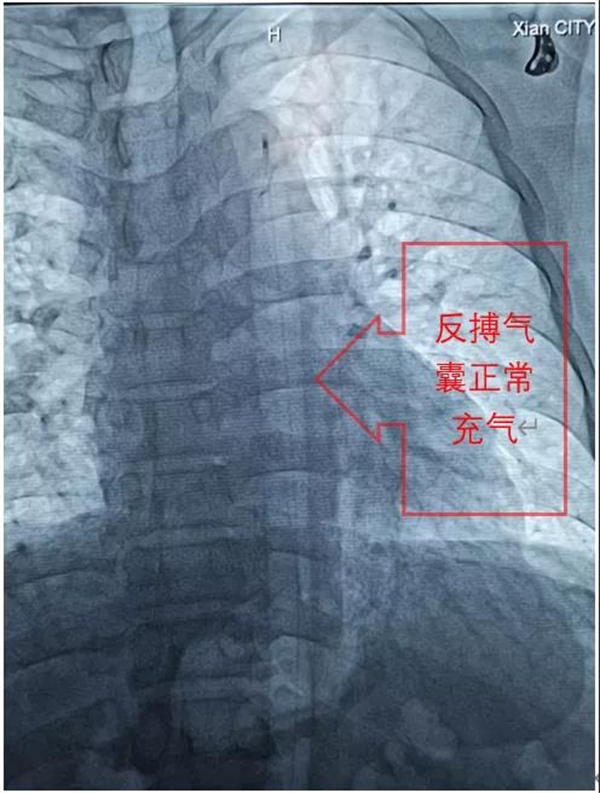

在刘毅龙主治医师的协助下,张拓伟副院长短时间顺利完成反搏球囊置入,随后韩延琪护师娴熟地完成连通管路,并精细调整反搏心电/血压触发比例,伴随着反搏气囊规律的充排气声,患者血压很快稳定在130/80mmHg左右,病情趋于平稳。随后,在张拓伟副院长的指导下,刘毅龙主治医师顺利完成后续的支架植入、高压后扩张等操作。当一条完整的血管和澎湃的血流重新呈现在眼前,患者胸痛症状完全缓解时,所有人紧绷的神经才放松下来,随后韩延琪护师根据心电/血压调整IABP的反搏触发等参数,患者病情稳定并安返病房。

IABP(主动脉球囊反搏术)是一种通过机械手段,辅助全身血液循环的技术。通过动脉系统植入一根带气囊的导管到左锁骨下动脉开口远端和肾动脉开口上方的降主动脉内。在心脏舒张期,气囊充气,在心脏收缩期前,气囊放气,达到辅助心脏的作用,从而增加冠状动脉供血和改善心肌功能。西安市中医医院心血管院目前正式启动该技术用于危重病患者的抢救和治疗。